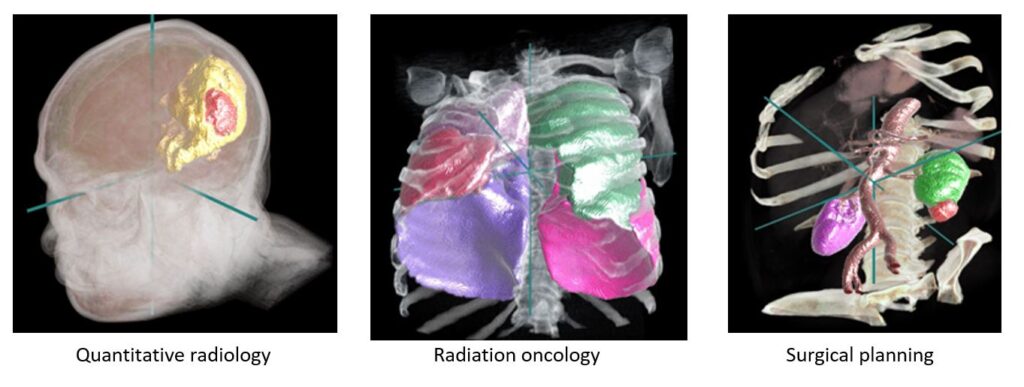

Radiology and surgery planning with CT images

The InnerEye-DeepLearning Toolkit (opens in new tab) makes it easy to use pre-configured neural networks, such as UNet3D, or bring-your-own-models (opens in new tab) for CT images. Potential use cases for this are quantitative radiology and surgery planning. Use of the Gateway and Inference Services will require additional software engineering effort by you. Support for these use cases is via GitHub Issues on the relevant repositories only.